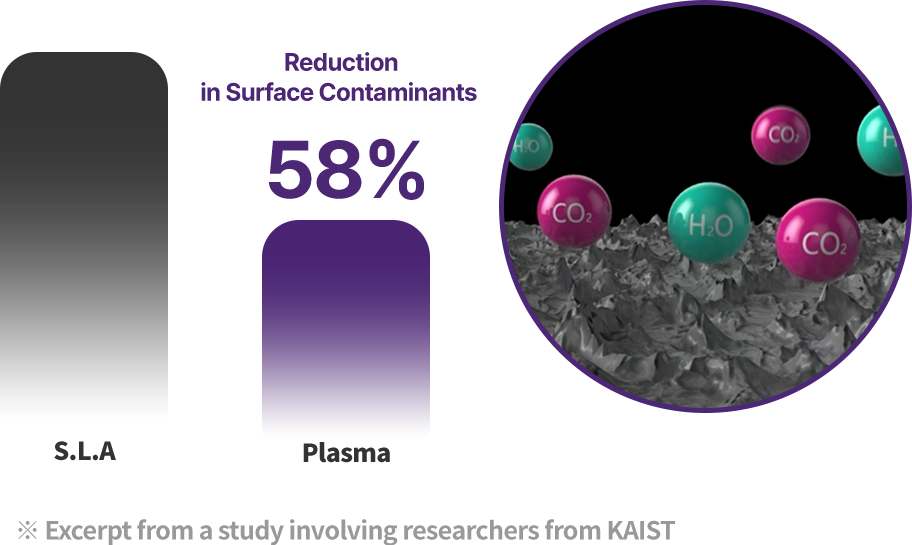

Plasma Surface Treatment Matters

During manufacturing, shipping, and long-term storage,

hydrocarbons can build up on the implant surface over time,

which may reduce biocompatibility.

Plasma implants use high-energy plasma

to remove hydrocarbons

and reactivate the surface for higher biocompatibility.

During manufacturing, shipping, and long-term storage, hydrocarbons can accumulate on the implant surface, reducing biocompatibility. Plasma implants remove hydrocarbons with high-energy plasma and reactivate the surface for higher biocompatibility.

Plasma treatment helps remove impurities left on the implant surface and improves surface hydrophilicity for better biocompatibility. Thanks to these benefits, plasma technology helps improve implant success and serves as a key factor for faster recovery.

Creating a safer implant surface through removal of surface impurities

Improved early protein attachment through organic removal and surface activation